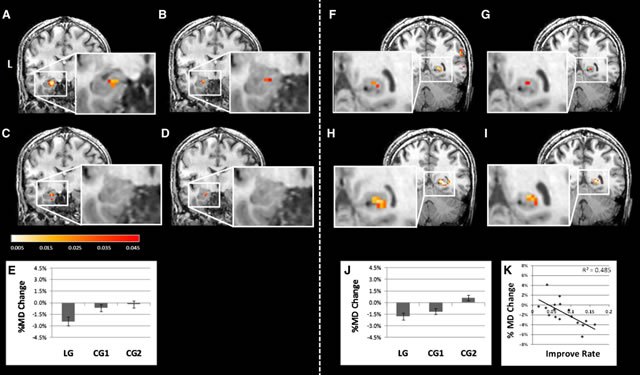

Мы знаем о невероятной пластичности мозга, но, конечно же, не все. Недавнее исследование ученых из Израиля (Sagi et al., 2012) продемонстрировало доказательства скорости нейропластичности.

Структурные изменения мозга могут быть наблюдаемы через десятки минут обучению чему-то новому. Используя диффузионное тензорное сканирование (diffusion tensor imaging, DTI) томографом, ученые смогли увидеть изменения в гиппокампе уже после двух часов видеоигры. В экспериментах с крысами было установлено точно, что такие изменения связаны с нейротропным фактором мозга (brain derived neurotropic growth factor, BDNF), протеином, который отвечает за поддержку, рост и развитие нейронов. Вероятно, у людей задействован тот же механизм.

Что это означает? Вы можете изменить свой мозг всего за 2 часа, достаточно для заметных, или не совсем заметных, изменений в поведении. Всего лишь два часа танцев, или новой компьютерной игры превратят вас в несколько другого человека, в буквальном смысле. Ну, и конечно, это опять подтверждает, что видеоигры — очень хорошая штука!

Sagi, Y., Tavor, I., Hofstetter, S., Tzur-Moryosef, S., Blumenfeld-Katzir, T., & Assaf, Y. (2012). Learning in the fast lane: New insights into neuroplasticity. Neuron, 73(6), 1195-1203.

Изображение и графики — из Sagi et al., 2012.